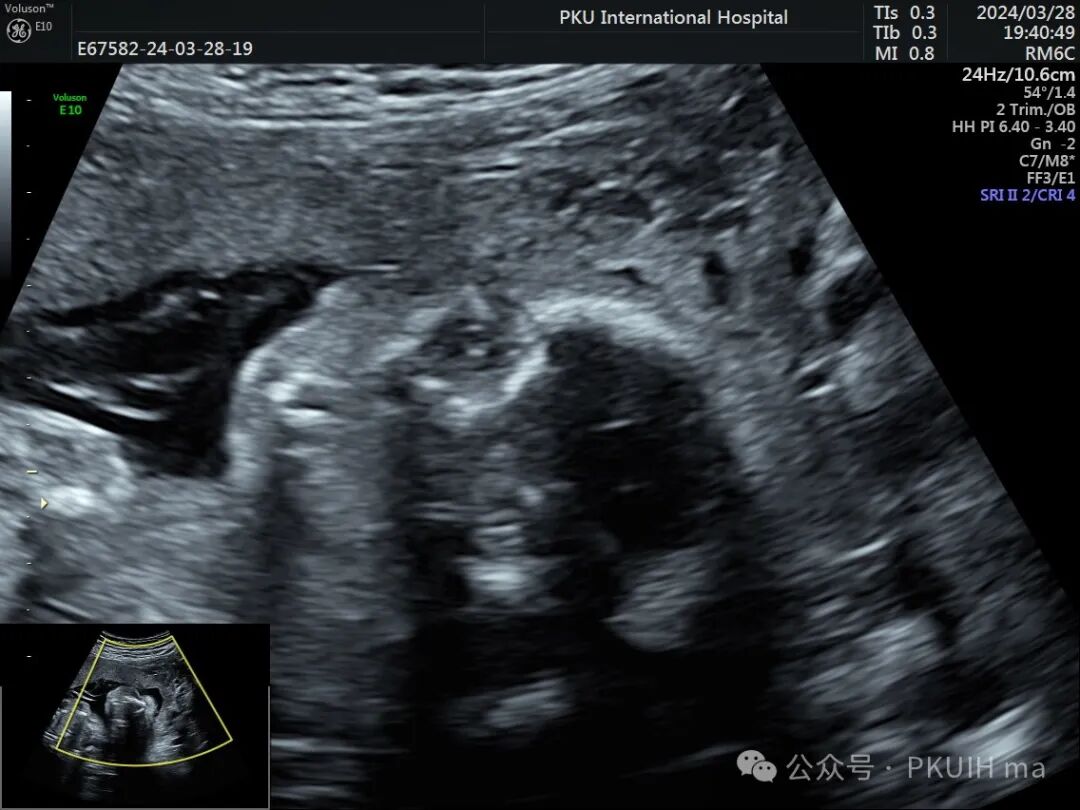

双眼球对比观察两眼球发育不对称,右眼明显发育小

实时动态观察双眼发育不对称,右眼小;两侧眼球内晶状体、玻璃体均可见,右侧晶状体小,晶状体后缘玻璃体内见不规则的高回声区。

PHPV的超声表现:一侧眼球晶状体后方可见Y形高回声或强回声条带,或者是晶状体后方圆形或圆弧状高回声团块(直接征象);同时伴有患侧眼球小,晶状体形态异常,眼轴短,部分有玻璃体浑浊。双眼发病极为罕见,表现双层晶状体浑浊,内见不规则强回声或高回声带。CDFI:部分病例可见增生的玻璃体动脉内见血流信号。该病容易反复发生眼内出血,纤维血管性肿块的收缩可能对视网膜产生牵拉,导致视网膜脱离。因此,眼部超声表现可能会随着妊娠进展而改变。